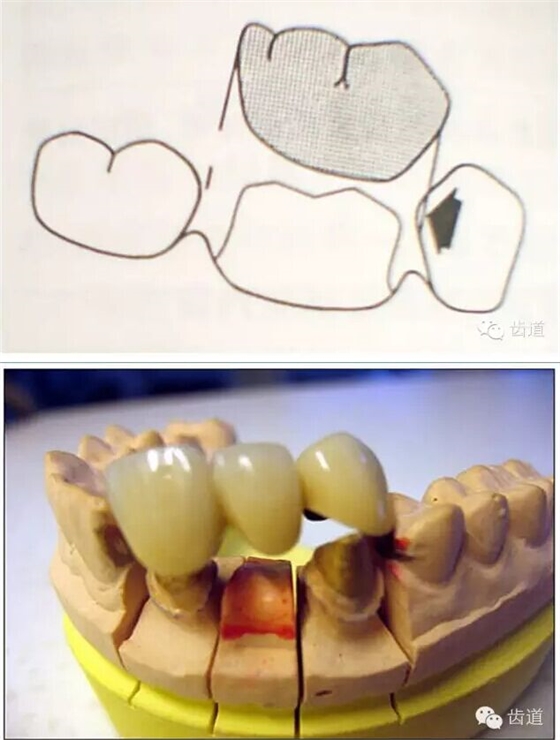

74.jpg

75.png

76.png

77.png

78.png

79.png

80.png

81.png

82.png

83.png

84.png

85.png

86.png

87.png

88.png

89.jpg

90.png

91.png

92.png

93..jpg

94.png

95.jpg

96.png

97.png

98.png

99.jpg

100.png

101.png

102.png

103.jpg

104.png

105.png

106.png